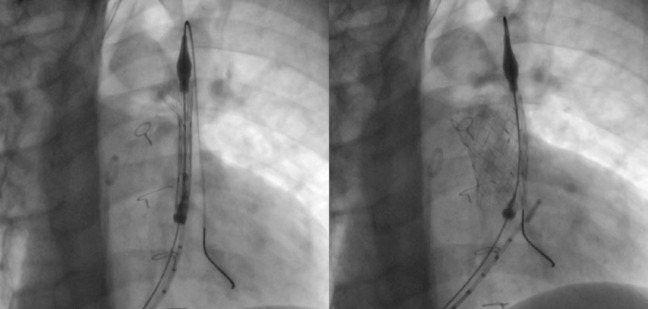

前言和目的:先天性心脏缺陷合并右心室流出道狭窄的手术常导致明显的肺返流,长期需要肺动脉瓣置换术。尽管发展了球囊式可膨胀假体,但原生RVOT经常扩张超过这些瓣膜允许的最大直径。为了允许经皮肺动脉瓣植入术(PPVI)在这些患者中,临床试验已经开始使用自膨胀假体,包括PULSTA瓣膜。本研究的目的是报告在三家西班牙医院使用该瓣膜的初步经验。方法:描述性研究采用PPVI配合PULSTA假体治疗先天性RVOT合并肺返流患者的效果。结果:纳入10例患者,平均年龄15±2.8岁。所有患者的植入都很成功,在手术过程中没有发生重大并发症。平均随访时间18个月[范围,2-35个月]。8例患者在6个月时进行心脏磁共振检查,发现舒张末期平均容积(131.7±31.7 mL/m2 vs 100.3±28.9 mL/m2)和收缩末期平均容积(68±20.8 mL/m2 vs 57±18.5 mL/m2)减少。结论:PULSTA假体是一种安全、可行、有效的替代方案,可用于原发性扩张性RVOT患者的PPVI。由于可用的随访数据有限,需要进一步的研究来评估其长期安全性和耐久性。

Introduction and objectives: Surgery for congenital heart defects with right ventricular outflow tract (RVOT) stenosis often results in significant pulmonary regurgitation, requiring pulmonary valve replacement in the long term. Despite the development of balloon-expandable prostheses, the native RVOT frequently dilates beyond the maximum diameters allowed for these valves. To allow percutaneous pulmonary valve implantation (PPVI) in these patients, clinical trials have been initiated with self-expanding prostheses, including the PULSTA valve. The aim of this study was to report the initial experience with this valve at three Spanish hospitals.

Methods: Descriptive study presenting the results of PPVI with the PULSTA prosthesis in patients with native RVOT and pulmonary regurgitation.

Results: We included 10 patients with a mean age of 15 ± 2.8 years. The implantation was successful in all patients, with no major complications occurring during the procedure. The mean length of follow-up was 18 [range, 2-35] months. In 8 patients, cardiac magnetic resonance was performed at 6 months, revealing a reduction in mean end-diastolic volume (131.7 ± 31.7 mL/m2 vs 100.3 ± 28.9 mL/m2) and end-systolic volume (68 ± 20.8 mL/m2 vs 57 ± 18.5 mL/m2).

Conclusions: The PULSTA prosthesis offers a safe, feasible, and effective alternative for PPVI in patients with native dilated RVOT. Due to the limited available follow-up data, further studies are needed to assess its long-term safety and durability.